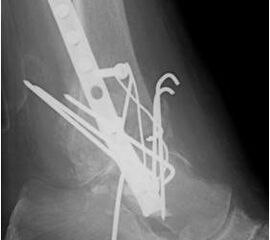

• Revision einer gescheiterten Fusion des OSG/ USG (Abbildung 3, Abbildung 4).

• Pseudarthrosen (Abbildung 5, Abbildung 6).

• Pseudarthrose (Abbildung 15).